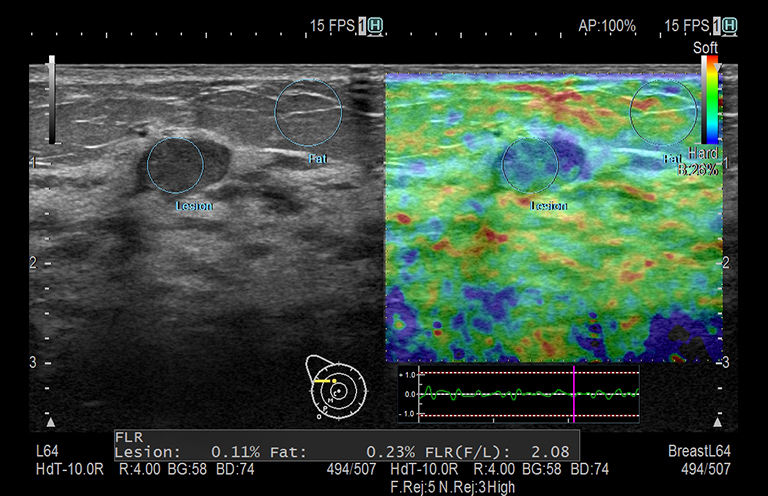

Aplicación: Mama

Función/análisis: RTE (ASR/AFS)

Comentarios: Mama